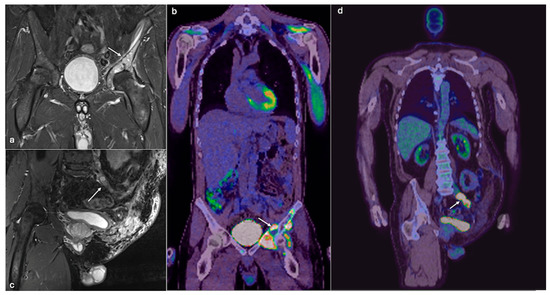

4.1. Osteosarcoma

- Plaza de Las Heras, I.; García Cañamaque, L.; Quílez Caballero, E.; Camacho-Arias, M.; Cárdenas Soriano, M.D.P.; Martel Villagrán, J. Positron emission tomography-magnetic resonance imaging applications in pediatric musculoskeletal tumors. Quant. Imaging Med. Surg. 2024, 14, 7825–7838. [Google Scholar] [CrossRef] [PubMed] [PubMed Central]